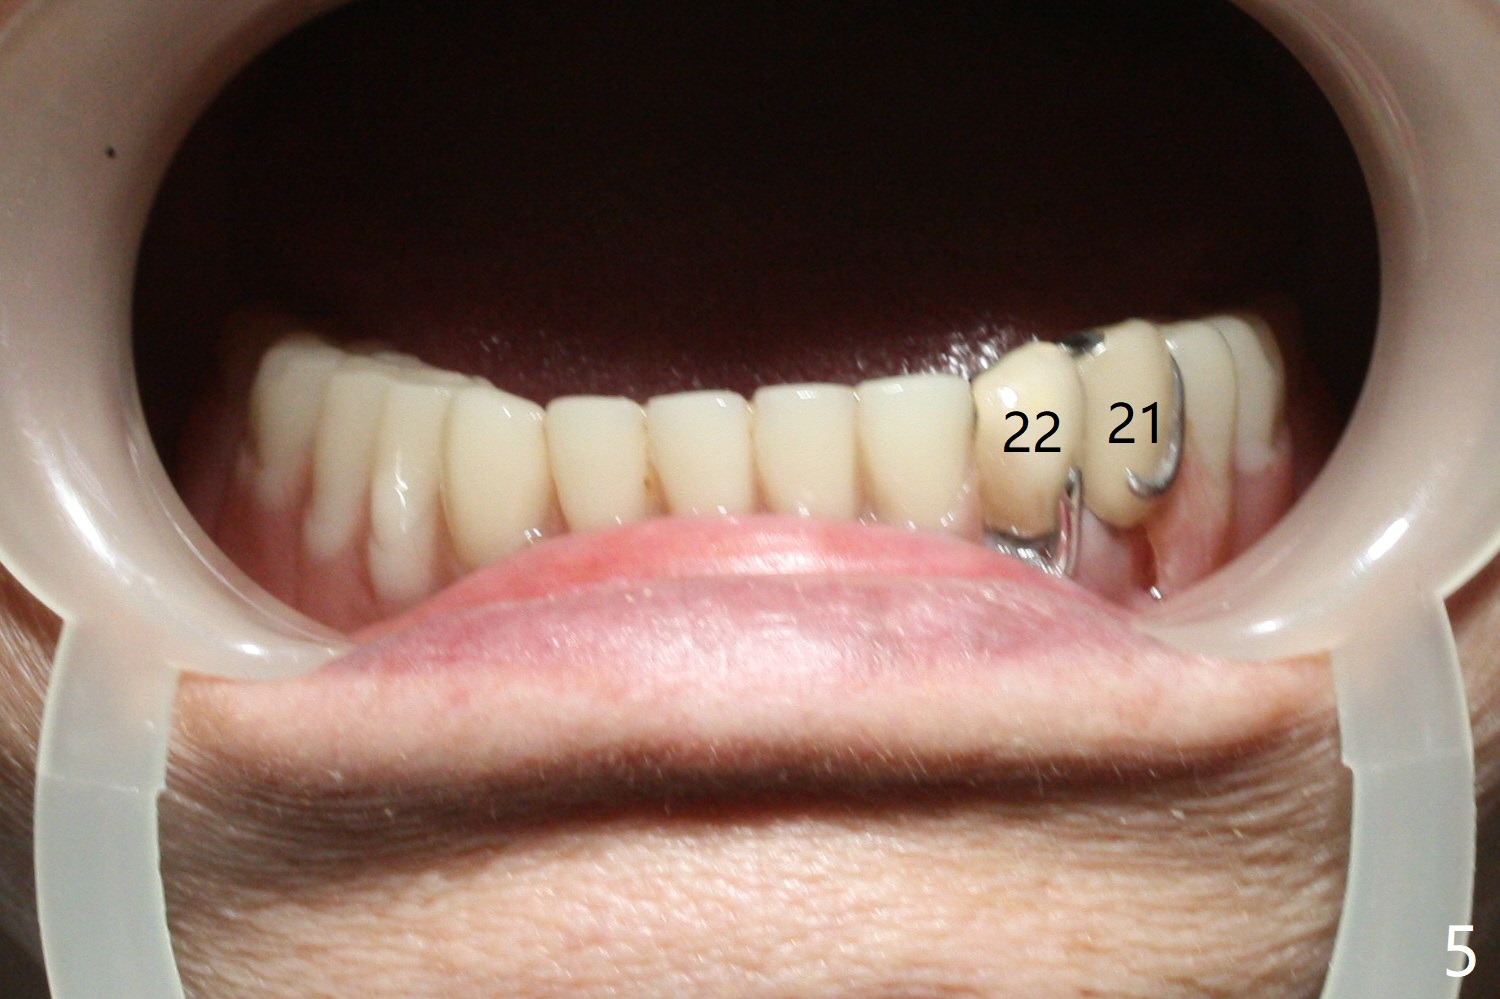

A 79-year-old woman is not pleased with cross bite and no tooth exposure of the upper complete denture (Fig.1-4). Her immediate concern is the loose lower RPD (Fig.5) after loss of the tooth #21 (Fig.6). The tooth #22 has mobility II. SM narrow implants will be placed at #22 and 27 immediately after #27 extraction (Fig.7,8). Ball abutments are going to be inserted prior to soft reline of the lower RPD. Prepare an acrylic bur to make a receptacle in the RPD for #27 abutment and high speed handpiece to section the tooth #22 as a denture tooth (prepare hard pink acrylic)